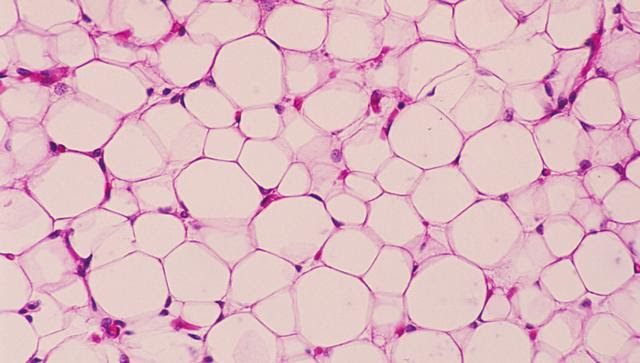

研究團隊通過藥物,將白色的脂肪細胞變成了棕色的燃燒脂肪細胞,讓我們的身體不再進行保存。同時雖然這種方法有一定的副作用,但是如果針對身體特定的部位進行限制使用,那麼產生的副作用影響非常有限。

這項技術利用的是奈米顆粒藥物存儲的疏水性內核,對藥物輸送系統和醫療設備使用PLGA聚合物,同時將目標嵌入蛋白分子發現組織和血管內的脂肪細胞,將納米粒子變成“導彈”,尋找特定的脂肪細胞並且釋放藥物來進行改變。